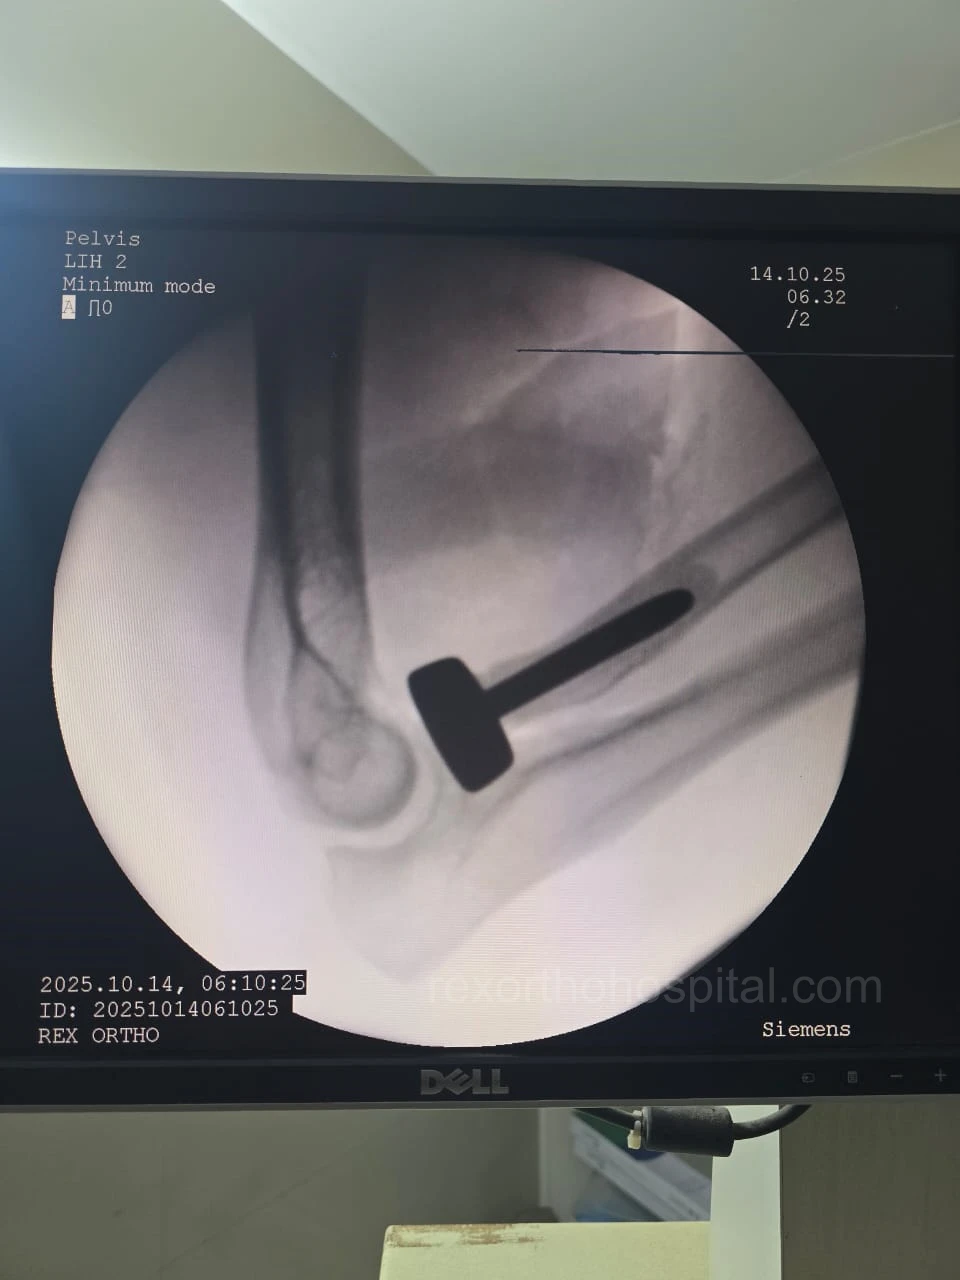

Elbow stiffness treatment aims to restore smooth movement and reduce pain caused by injury, arthritis, or long-term immobility. Our approach improves flexibility and helps regain everyday function.

From diagnosis to surgery and recovery, our team ensures you receive expert treatment and individual attention throughout your treatment journey